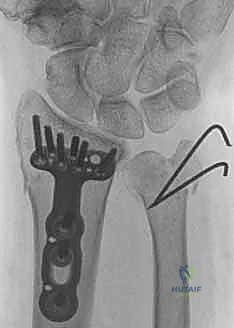

2. كسور رأس الزند (Ulnar Head Fractures)

رأس الزند هو الجزء المفصلي الدائري الذي يدور حوله الكعبرة.

* كسور مفصلية (Articular Fractures): تمتد خطوط الكسر لتشمل الغضروف المفصلي. إذا لم يتم إعادة العظام إلى وضعها التشريحي المثالي (Anatomic Reduction)، فإن المريض سيكون عرضة للإصابة بخشونة المفاصل المبكرة (Post-traumatic Osteoarthritis) وفقدان القدرة على تدوير الساعد.

* كسور غير مفصلية: تقع تحت السطح المفصلي مباشرة، ولكنها قد تؤدي إلى تشوه في زاوية رأس الزند.

ثانياً: العلاج الجراحي (Surgical Intervention)

متى يقرر الدكتور هطيف ضرورة التدخل الجراحي؟

1. عدم الاستقرار (Instability): إذا كان المفصل الزندي الكعبري البعيد (DRUJ) غير مستقر بعد تثبيت كسر الكعبرة.

2. الانزياح (Displacement): إذا كان الكسر في قاعدة الناتئ الإبري منزاحًا بأكثر من 2 ملم.

3. الكسور المفصلية: أي كسر يخل بتطابق السطح المفصلي لرأس الزند.

4. الكسور المفتتة: في الجزء الكردوسي التي تؤدي إلى قصر عظم الزند.

5. الكسور المفتوحة (Open Fractures): حيث يبرز العظم من الجلد، وتتطلب جراحة طارئة لتنظيف الجرح وتثبيت الكسر لمنع العدوى.

خطوات التدخل الجراحي الدقيق مع الأستاذ الدكتور محمد هطيف

تُعد جراحات المعصم والزند من الجراحات الدقيقة التي تتطلب مهارة عالية، وهو المجال الذي يتفوق فيه الأستاذ الدكتور محمد هطيف بفضل استخدامه لتقنيات الجراحة المجهرية (Microsurgery) والأدوات الجراحية ذات التقنية العالية.

1. التخطيط ما قبل الجراحة (Pre-operative Planning)

يقوم الدكتور هطيف بدراسة الأشعة المقطعية ثلاثية الأبعاد بدقة، ويختار نوع وحجم الصفائح المعدنية (Plates) والمسامير (Screws) المناسبة لكل مريض بناءً على حجم العظم ونوع الكسر.